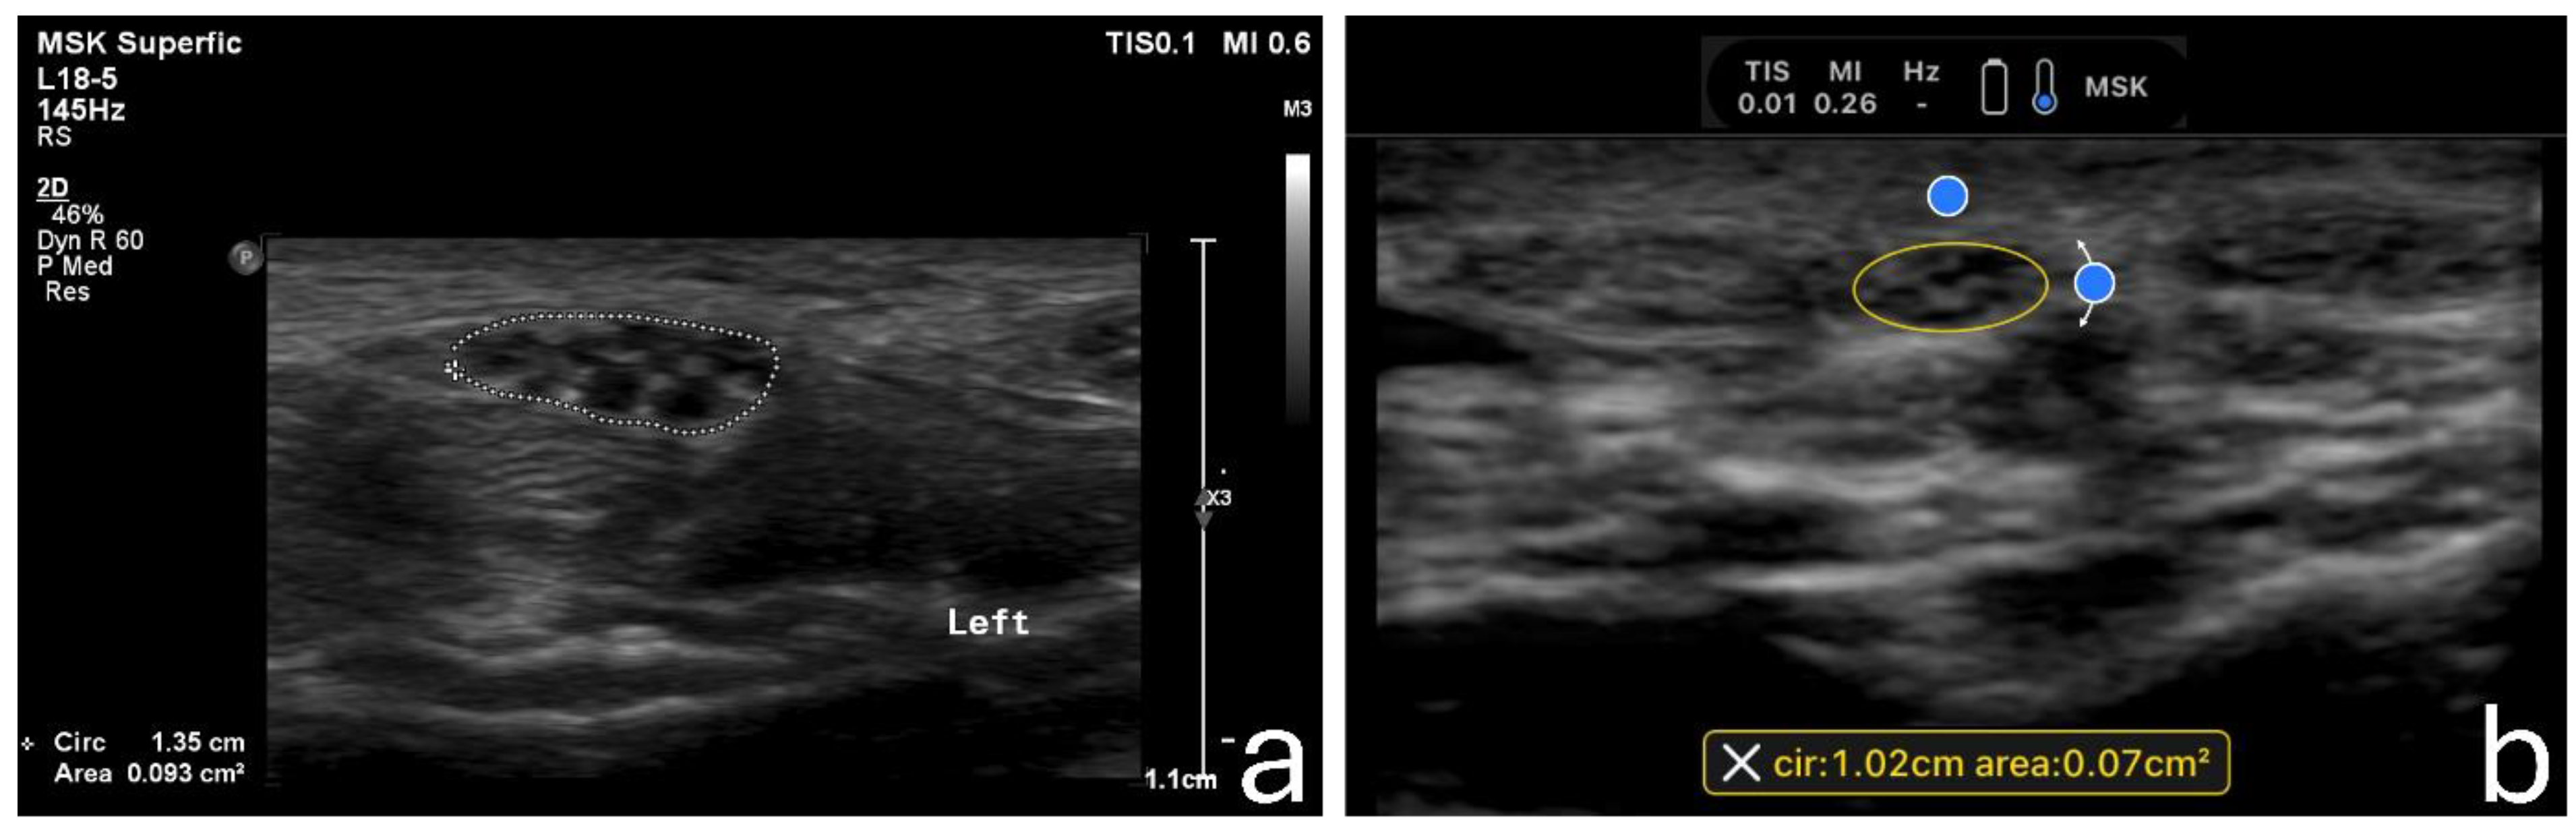

2.4. Image Acquisition